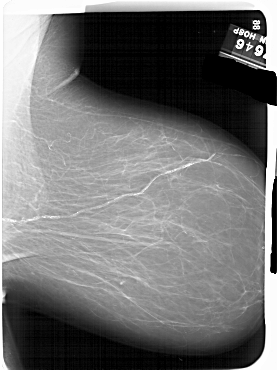

A_1551_1.RIGHT_MLO

LEFT_MLO LINES 6541 PIXELS_PER_LINE 5206 BITS_PER_PIXEL 12 RESOLUTION 43.5 OVERLAY

RIGHT_MLO LINES 6646 PIXELS_PER_LINE 4981 BITS_PER_PIXEL 12 RESOLUTION 43.5 NON_OVERLAY